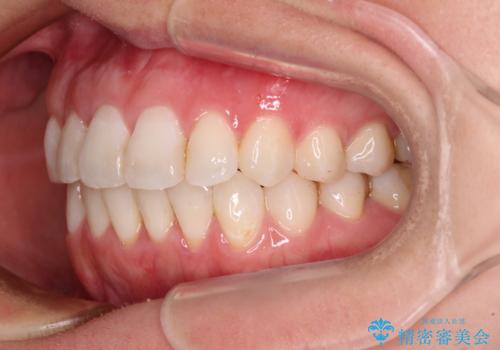

長年気にしていた前歯 インビザラインで目立たず改善

- ワイヤーではない矯正治療があると聞いたとのことで来院された患者様です。

長年前歯のデコボコを気にしていたもののワイヤー矯正に抵抗があり躊躇していたそうですが、インビザラインなら治療してみたいとのことで相談にいらっしゃいました。

インビザライン適用の歯列であったため、歯と歯の間を削るIPRを用いて改善することとしました。

下顎前歯の叢生が顕著な場合、歯列改善後に歯と歯と歯肉の間にブラックトライアングルという隙間ができてしまいます。

軽減することはできますが、完全に解決することは矯正治療のみでは不可能なため、リスクとして事前に周知しておく必要があります。